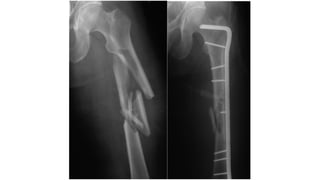

This document discusses femoral fractures, categorized by their location and severity, with classifications such as Garden classification. It outlines the types of fractures, including valgus impacted, non-displaced, partially displaced, and fully displaced, along with their surgical treatment options. Additionally, it briefly describes distal femur fractures, which occur just above the knee joint.